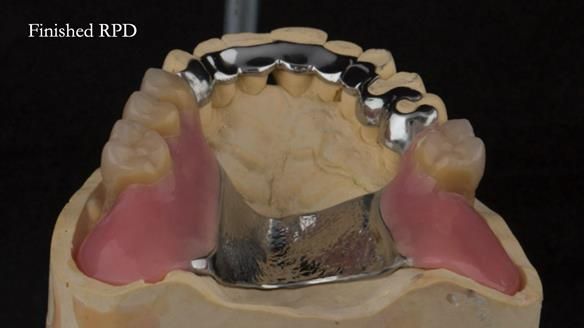

Instead, we made a Scandinavian-style, metal-based lower RPD.

The upper jaw

A metal-based upper RPD was made,

with metal backings incorporated to future-proof the design

should further teeth fail.

The way Rowan lengthened the teeth — particularly in the upper RPD — to match the existing gingival recession on the remaining teeth was superb. The dentures sit naturally within the context of the rest of the mouth.